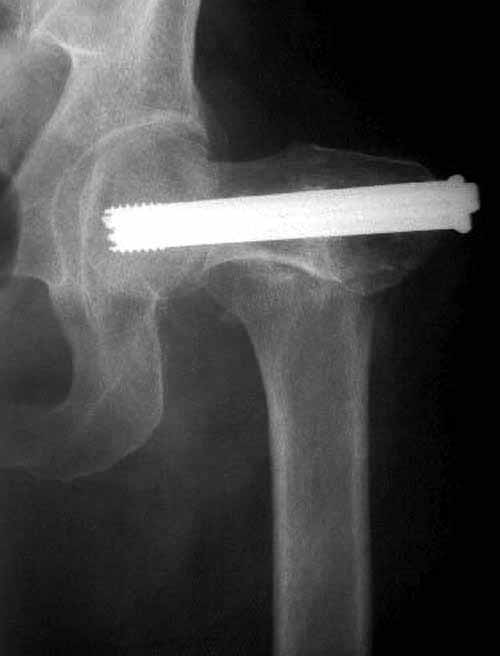

Пациентка Ш. 76 лет, 11 дней назад прооперирована по поводу вколоченного субкапитального перелома шейки левой бедренной кости, 3-мя канюлированными винтами. Вчера пациентка упала в палате. И вот результат- подимплантатный подвертельный перелом левой бедренной кости. Уважаемые коллеги, пожалуйста посоветуйте какой метод дальнейшего лечения предпринять дальше.Соматически пациента повышенного питания, страдает варикозной болезнью нижних конечностей.Из предложенных вариантов коллег - целллокастовая укороченная кокситная повязка, скелетное вытяжение сроком на 40-45 суток - отпали сразу, так как необходимо активизация пациентки.На данный момент рассматриваем следующие варианта реостеосинтеза:(наличие технических возможностей) 1. Длинная Gamma 3 Stryker (с предварительной интраоперационной фиксацией головки спицами).2. Трохантерный штифт DePuy с 2-мя метафизарными винтами в проксимальном отделе, (также с интраоперационной фиксацией головки спицами. Очень настораживает стабильность фиксации с проксимальном отделе с связи с выборкой костной ткани ранее находящимися там канюлированными винтами. Сейчас пациентка находится на скелетном вытяжении, с дисциплинирующим грузом. Операция планируется после праздников. Заранее извиняемся за качество и неполное соответствие проекций на R-ммах (R-служба отдельная песня). При интраоперационном ЭОП-контроле винты в аксиальной проекции разнесены по шейке.

Перелом, как мне кажется, "чрезимплантный." Мы бы убрали два нижних винта, верхний не трогали (для ротационной стабильности в последующем)+ поставили-бы DHS. Направляющую спицу для шеечного винта вводите до удаления нижних и тогда потеря головкой девственности не будет иметь такого значения.

Пластину поверх или мимо канюлированных винтов.

Как вариант (если не будет места) - оставить один винт в шейке, приладить пластину, второй винт ввести на старое место через пластину, о третьем винте забыть - хватит ей и двух при таком раскладе.

Согласен с Николаем, винты распоожены так, чтобы эту "мину" заложить. И два внизу, и не должны, даже если один он там, они входить ниже уровня малого вертела, это резко повышает риск подвертельного перелома. Что до остеосинтеза - учитывая 76 лет, более подходящей представляется большего диаметра винт в шейке, то есть гамма.

У больных с ожирением и соматическими заболеваниями нежелательно открывать место перелома. Гвозди от DePuy с двумя шурупами рассчитаны для переломов бедра, и приходилось их применить для фиксации подвертельных переломов, но более адекватную фиксацию создает Gamma 3.

Здесь подобный случай, где стрессовый перелом обнаружен через 2 недели после фиксации. Применен Blade Plate с дополнительными шурупами.